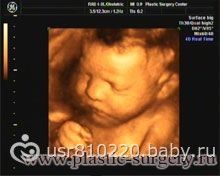

хотелось бы что бы качество изображения было четкое и цветное (желтого цвета, не знаю как правильно называется)

хотелось бы вот такого изображения!!! такое делают в тонусе?